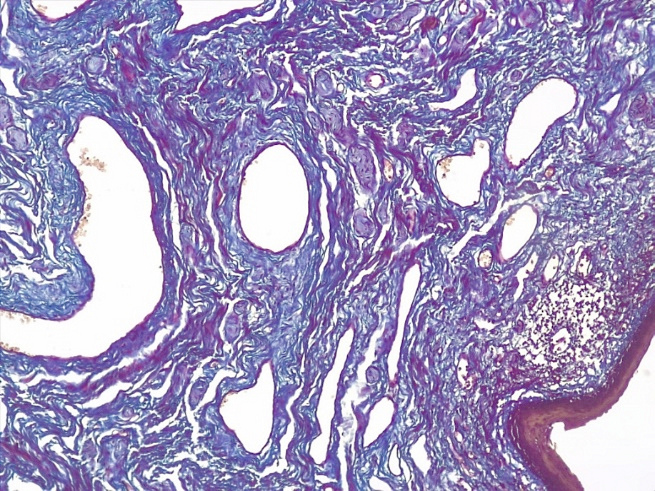

Что касается состояния микроциркуляторного русла при склерозирующем варианте течения СЛВ, то количество кровеносных сосудов было резко редуцировано как в поверхностных, так и в глубоких отделах дермы. В стенках кровеносных сосудов отмечалось развитие склероза и гиалиноза, что указывало на длительное нарушение сосудистой проницаемости в этой зоне (рис. 10 и 11).

Рис.10. Склерозирующий вариант СЛ вульвы. Под атрофичным многослойным плоским эпителием находится фиброзная ткань с единичными редуцированными тонкостенными сосудами в поверхностных слоях дермы с отложением масс гиалина, умеренно выраженной лимфо-гистиоцитарной инфильтрацией глубоких слоев дермы (ШИК-реакция по Хочкиссу, х100)

Fig.10. The sclerosing variant of the vulva SL. Under the atrophic multilayered squamous epithelium there is fibrous tissue with single reduced thin-walled vessels in the surface layers of the dermis with deposition of hyaline masses, moderate lymph-histiocytic infiltration of the deep layers of the dermis (CHIC-Hotchkiss reaction, x 100)

Рис.11. Склерозирующий вариант СЛ вульвы. Резкая атрофия клеток эпидермиса с участками гиперкератоза с выраженным фиброзом поверхностных и глубоких слоев дермы со склерозом и гиалинозом немногочисленных сосудов микроциркуляторного русла (окраско по пикро-Маллори, х200)

Fig.11. The sclerosing variant of the vulva SL. Sharp atrophy of epidermal cells with areas of hyperkeratosis with pronounced fibrosis of the superficial and deep layers of the dermis with sclerosis and hyalinosis of a few vessels of the microcirculatory bed (picro-Mallory coloring, x 200)